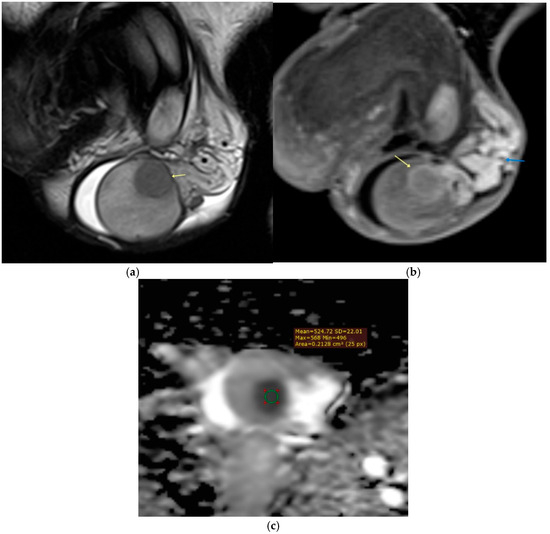

Background: Magnetic resonance imaging (MRI) plays an increasingly important role in the evaluation of scrotal and penile disorders, complementing ultrasonography in cases where findings are equivocal or complex. With its superior soft-tissue contrast, multiplanar capability, and advanced functional sequences, MRI provides unparalleled anatomic and tissue characterization across a wide range of male genital pathologies. Summary: This review summarizes current clinical applications of MRI in scrotal and penile imaging and discusses its diagnostic value, protocol optimization, and interpretive features. In scrotal pathology, MRI accurately differentiates torsion, trauma, infection, and neoplasms, aiding in the distinction between benign and malignant testicular lesions and supporting testis-sparing management. Quantitative diffusion and perfusion metrics further refine lesion characterization. In andrology, MRI biomarkers such as apparent diffusion coefficient (ADC), magnetization transfer ratio (MTR), and proton spectroscopy serve as promising non-invasive indicators of spermatogenic activity in male infertility. In penile imaging, MRI enables precise local staging of carcinoma, assessment of plaque morphology and activity in Peyronie’s disease, evaluation of tissue viability in priapism, and detection of prosthesis-related complications. Conclusions: MRI has become an essential problem-solving tool in the assessment of scrotal and penile diseases, enhancing diagnostic confidence and surgical planning. Future directions include protocol standardization, quantitative parameter validation, and the integration of radiomics and artificial intelligence to improve reproducibility and clinical impact. Full article